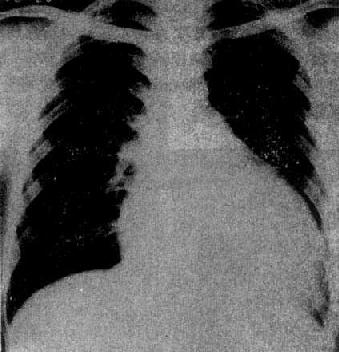

X线表现(图3-2-20),早期心大小和形状可以正常,以后心中度至高度增大,一般为双心室增大,但以左心室增大为显著,呈主动脉型;心搏动普遍减弱;肺血管纹理正常或增多,心力衰竭时,出现肺瘀血及间质性肺水肿主动脉球一般不增大,有时因心排血量减少而缩小。继发性心肌病,病变好转后,心影恢复正常。

原发性心肌病(扩张型)

图3-2-20 原发性心肌病(扩张型)

心明显增大,以向左侧增大明显,

主动脉球较小,肺纹理正常